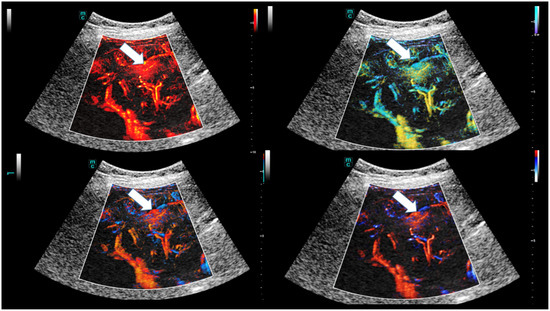

- Dropco, I.; Kaiser, U.; Wagner, L.; Brunner, S.M.; Schlitt, H.J.; Stroszcynski, C.; Jung, F.; Yi, D.; Herr, W.; Jung, E.M. Color Mapping using Ultrasound System-integrated Perfusion Software for Evaluation of Focal Liver Lesions: A Possible First Step for More Independent Reading. J. Gastrointestin. Liver Dis. 2023, 32, 479–486. [Google Scholar] [CrossRef]

- Schelker, R.C.; Andorfer, K.; Putz, F.; Herr, W.; Jung, E.M. Identification of two distinct hereditary hemorrhagic telangiectasia patient subsets with different hepatic perfusion properties by combination of contrast-enhanced ultrasound (CEUS) with perfusion imaging quantification. PLoS ONE 2019, 14, e0215178. [Google Scholar] [CrossRef]

- Schelker, R.C.; Barreiros, A.P.; Hart, C.; Herr, W.; Jung, E.M. Macro- and microcirculation patterns of intrahepatic blood flow changes in patients with hereditary hemorrhagic telangiectasia. World J. Gastroenterol. 2017, 23, 486–495. [Google Scholar] [CrossRef]